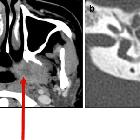

High-resolution temporal bone CT is routinely performed and may show:

- soft tissue density in the middle ear cavity

- thickened tympanic membrane

- bulging tympanic membrane

- tympanic perforation

Features seen in chronic rather than acute otitis media include:

- air-fluid level in the middle ear (effusion)

- bony erosion (less than 10%)

- adjacent sclerosis and hypopneumatisation of the mastoid